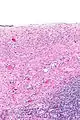

Los cistoadenomas serosos se diagnostican mediante examen histomorfológico, por patólogos. En general, son quistes uniloculares que contienen un líquido claro de color pajizo. Microscópicamente, el revestimiento del quiste consiste en un epitelio simple con cilios que puede ser columnar o plano.